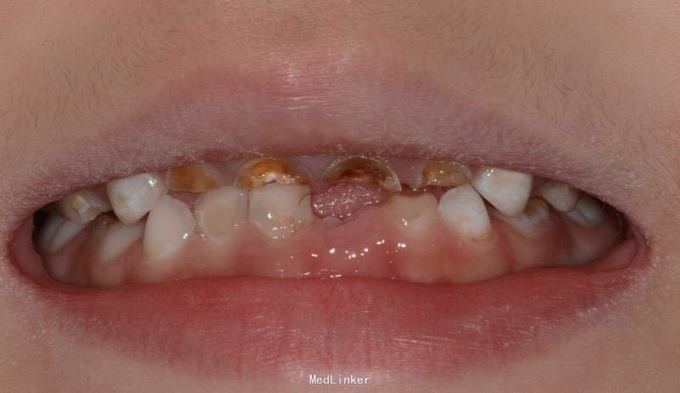

儿童6岁乳上前牙只剩牙根,唇侧牙龈有瘘管口半月,特来就诊

A1 B1 残根,可探及根管内,有黑褐色腐质物,扣(-),探(-),无松动,唇侧牙龈微红肿,各有一个瘘管口,压有浓液渗出物,A2 B2残根,呈黄褐色扣(-),探(-),无松动。